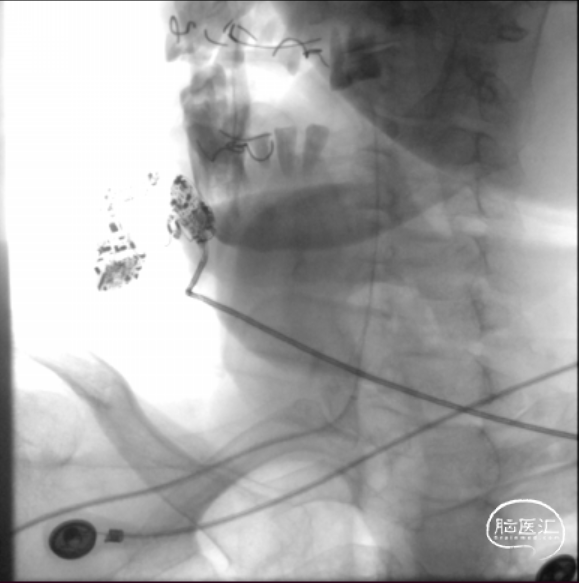

将微导丝头端置右侧大脑后动脉,沿微导丝引入2.0*10mm球囊,小心扩张狭窄段,撤出球囊后造影,原有狭窄较前稍好转,沿微导丝引入支架用微导管置于基底动脉,撤出微导丝,保留微导管,沿微导管引入3.5*15mm Neuroform EZ支架,缓慢释放,复查造影,狭窄较前明显好转,支架贴壁良好。

复查Dyna CT,颅内未见出血及造影剂外渗。